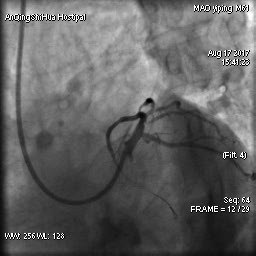

毛先生的血管在心臟左主干體部及分叉部都出現(xiàn)嚴(yán)重狹窄,僅一絲血流通過,前降支的血流已明顯減慢。難怪日常步行都會(huì)引起心絞痛,毛先生隨時(shí)都可能心臟驟停。

術(shù)前 心臟左主干末端嚴(yán)重狹窄

術(shù)后 心臟左主干末端狹窄解除,血流通暢